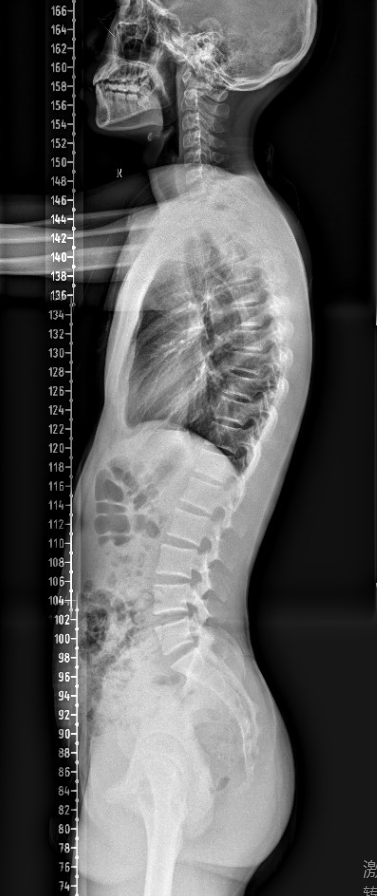

【影像】全脊柱X线示:胸曲过大,腰椎棘突偏左,髂骨右侧宽左侧窄,骨盆后倾。

腘绳肌及小腿三头肌挛缩,牵拉坐骨结节向下,骨盆后倾。患者腰椎棘突偏歪,椎体旋转,屈曲功能下降。患者坐位时骨盆后倾,当以屈腰代偿屈髋不足,因其屈腰受限,故以加大胸曲代偿,背部竖脊肌长期过度牵张而劳损,发为背痛。故操作时不治在上肌肉损伤(病之标),而疗在下之肌肉挛缩(病之本),不但效速,且能效久。